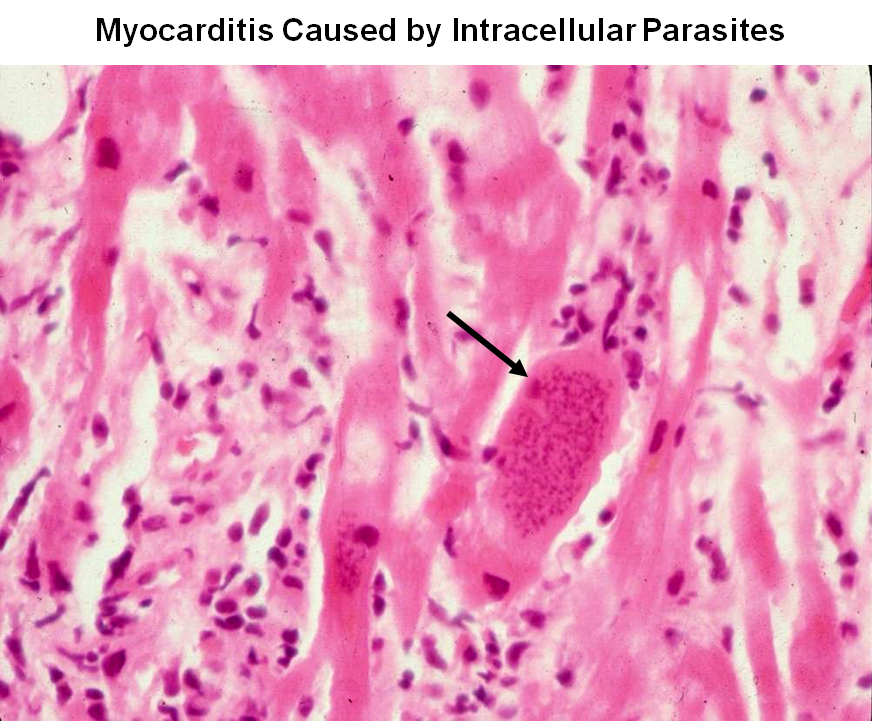

Межуточный миокардит: гистологические исследования

Раздел: Идеи и советы